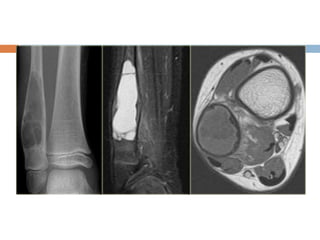

Aneurysmal bone cyst

 At any age ,more on young adults

 Any bone, more on long bone metaphysis

 Arises spontaneously or after degenaration or

hemorrhage in some other lesion.

 Pain is most common complain

 Large cyst may cause visible or palpable

swelling of bone.

 Malignant transformation does not occur

Xray

 Well defined radiolucent cyst

 Trabeculated and eccentrically placed

 In growing tubular bone, vertebrae and flat

bones

 In adult may confuse with GCT

 Marked ballooning of bone end

large cystic spaces separated by septa

containing giant cells and spindle cells.

The spaces may be filled with blood and

lack an endothelial lining